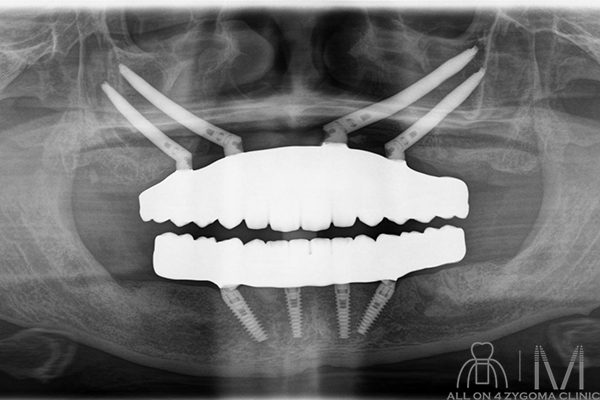

術後パノラマ画像所見

4本のザイゴマインプラントと4本のノーマルインプラントに8本のアバットメントを認める。上下とも最終補綴物を示唆する所見を認める。

最終補綴物セット後の口腔内所見

最終補綴物セット後の写真。上下顎のモノリシックジルコニアの上部構造である事が確認出来る、またアクセスホールを計8つ認め、オールオン4である事が確認出来る。上顎前突の改善を認める。

結果

上下顎オールオン4ザイゴマインプラント を行う事で、審美性の高いスマイルラインを獲得できた。 ご本人様からは「今回、下だけでなく上下の手術をして本当に良かったです。」との事だった。